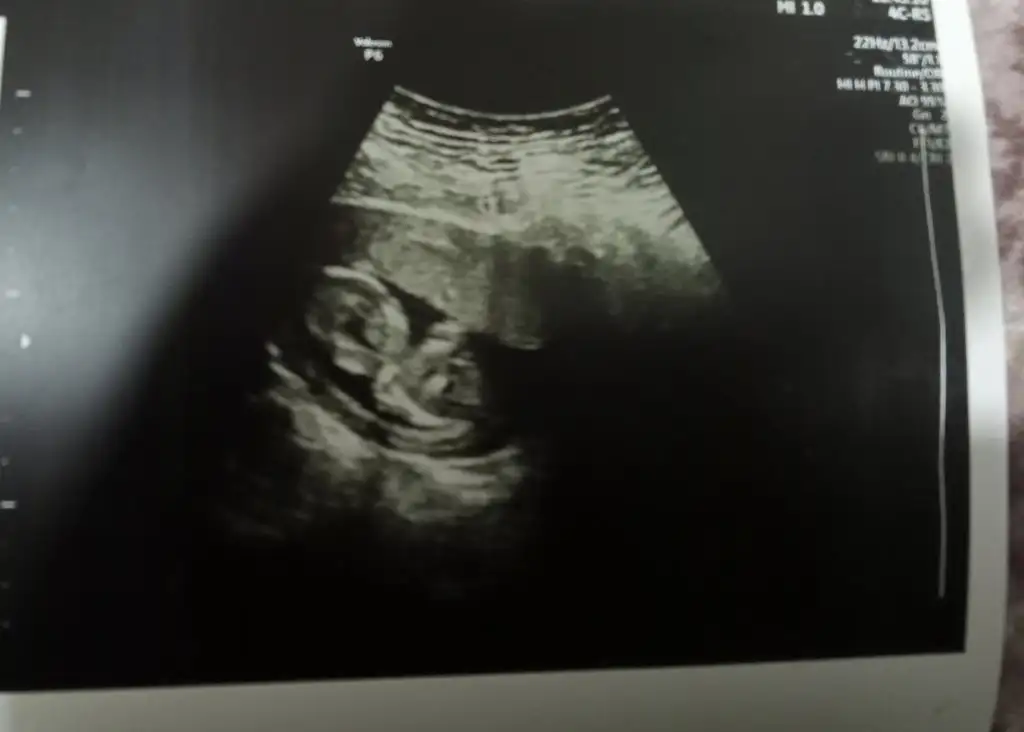

Nub Teorisinden anlayan arkadaşlar bakabilir mi

İlk haftalarda karışıyor canım yüksek ihtimalle kız demiş zaten bencede kız ☺️ sağlıkla gelsin 🙏

Saol canım ama bacagi kapalıydı çokta ayrıntılı bakmadı Bak böyleydi doktorda yüksek ihtimalle kız dedi

Eklentiler

• IMG_20211115_202906.webp

IMG_20211115_202906.webp

12,2 KB · Görüntüleme: 72